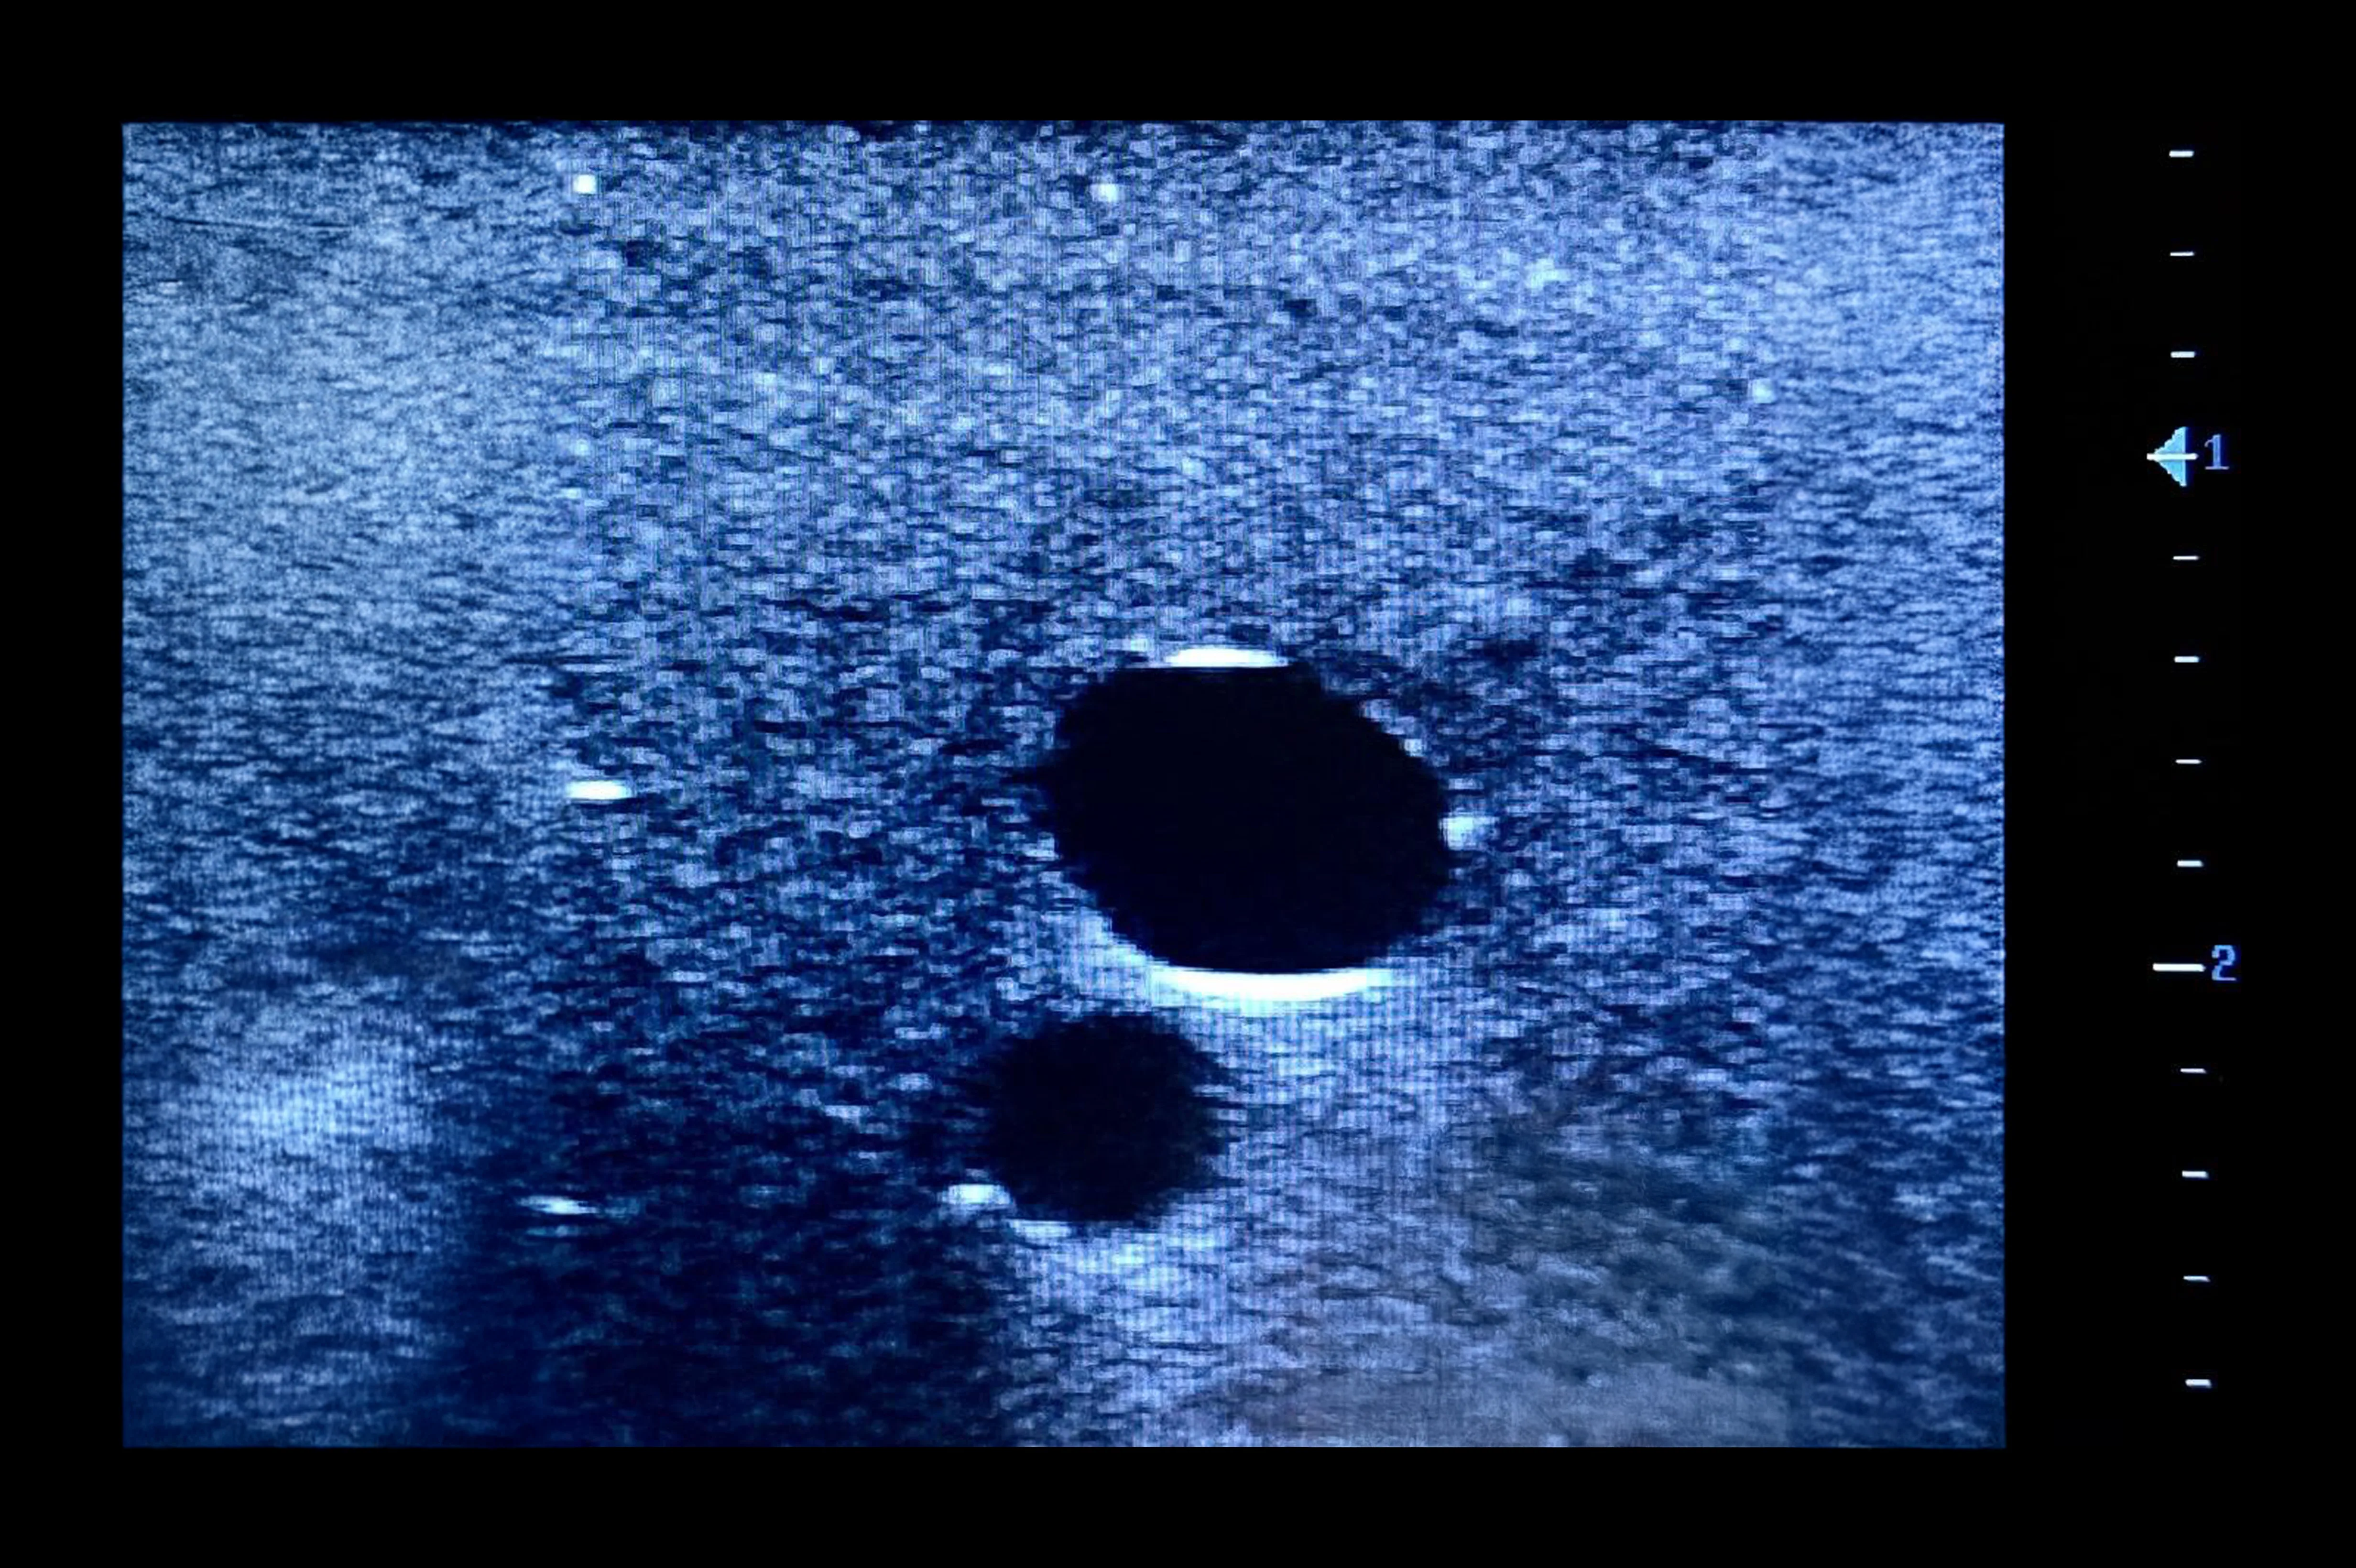

Designed for femoral vascular access training, this simulator features two vertically branched veins (approx. 8 mm diameter, 20 mm deep) with simulated calcifications. Lifelike echogenic material closely mimics human tissue, enabling realistic ultrasound-guided practice, probe control, and anatomy recognition in a safe, repeatable environment for both trainees and experienced clinicians.

- Identification of veins under ultrasound

- For femoral access with two vertically branched blood vessels with simulated calcifications

- Veins of diameters approximately 8 mm, located 20 mm below the surface of the simulator for vascular access

- Tubeless veins occlude when pressed either by hand or ultrasound probe

- Vein occlusion is visible under ultrasound